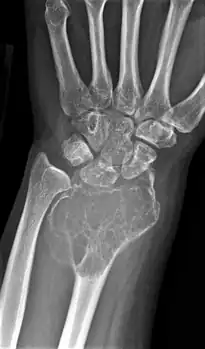

On X-ray, giant-cell tumors (GCTs) are lytic/lucent lesions that have an epiphyseal location and grow to the articular surface of the involved bone.[11] Radiologically the tumors may show characteristic 'soap bubble' appearance.[12] They are distinguishable from other bony tumors in that GCTs usually have a nonsclerotic and sharply defined border. About 5% of giant-cell tumors metastasize, usually to a lung, which may be benign metastasis,[13] when the diagnosis of giant-cell tumor is suspected, a chest X-ray or computed tomography may be needed. MRI can be used to assess intramedullary and soft tissue extension.

Front view X-ray. A well-defined expansile lesion in radius near wrist

Side view of same wrist

Front view X-ray one-year later it has grown